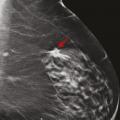

La tomosynthèse est une technique de mammographie développée depuis plus de 15 ans qui consiste non plus à acquérir deux images fixes du sein, mais un volume d’images, par un déplacement du tube de rayons X sur une angulation définie. Ainsi, le nombre d’images varie selon l’épaisseur du sein. L’avantage de cette technique est de s’affranchir d’une partie des effets masquants du tissu mammaire sur d’éventuelles lésions, et de mieux définir les contours des lésions bénignes et des cancers.

Cette technique permet d’augmenter le taux de détection des cancers, principalement invasifs, en particulier dans les seins denses de type C. Une récente étude prospective italienne a montré que la tomosynthèse mammaire deux incidences (face, oblique), associée à la vue synthétique (image 2D reconstruite à partir du volume 3D), permettait d’augmenter significativement le taux de cancers.8 Dans cette étude, 16 666 femmes asymptomatiques âgées de 50 à 69 ans ont été dépistées dans le programme de dépistage de Vérone avec une tomosynthèse deux incidences, comportant une analyse complémentaire de la vue synthétique. Les résultats ont été comparés à ceux de la précédente cohorte de dépistage de 2014, où les mammographies avaient été acquises uniquement en 2D (14 443 femmes).9 Le programme avec tomosynthèse et vue synthétique a permis une augmentation de détection de cancers invasifs significatifs par rapport au programme de dépistage 2D, avec un taux de détection de 9,30 versus 5,41 cancers pour 1 000 femmes. Ce qui est intéressant est que les cancers dépistés étaient plus souvent des cancers invasifs de stade 1 (72,3 % avec la tomosynthèse vs 50 % avec la mammographie 2D), avec moins de cancers in situ (9 % avec la tomosynthèse vs 26,9 % avec la mammographie 2D). Le taux de rappel était similaire entre les deux techniques (4 % pour la tomosynthèse vs 4,2 % pour la mammographie 2D). Ces résultats sont en accord avec les principales études prospectives et rétrospectives comparant l’apport de la tomosynthèse par rapport à la mammographie 2D.10 11